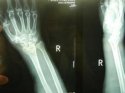

上一期51漫画在线登录页面免费阅读讲诉了患桡骨远端骨折的原因及其注意事项, 51漫画网官网免费仪品牌 51漫画在线登录页面免费阅读继续为您讲述桡骨骨折后如何更好的恢复。 1、俗话说伤筋动骨一百天,有钢板的在1年内每月到医院复

桡骨是人体前臂双骨之一,位于前臂外侧,大拇指一侧,分为一体和两端。是前臂长骨之一;蛙、蟾蜍等动物的桡骨与尺骨愈合成桡尺骨。 51漫画网官网免费仪厂家 51漫画在线登录页面免费阅读为您讲述桡骨引起的